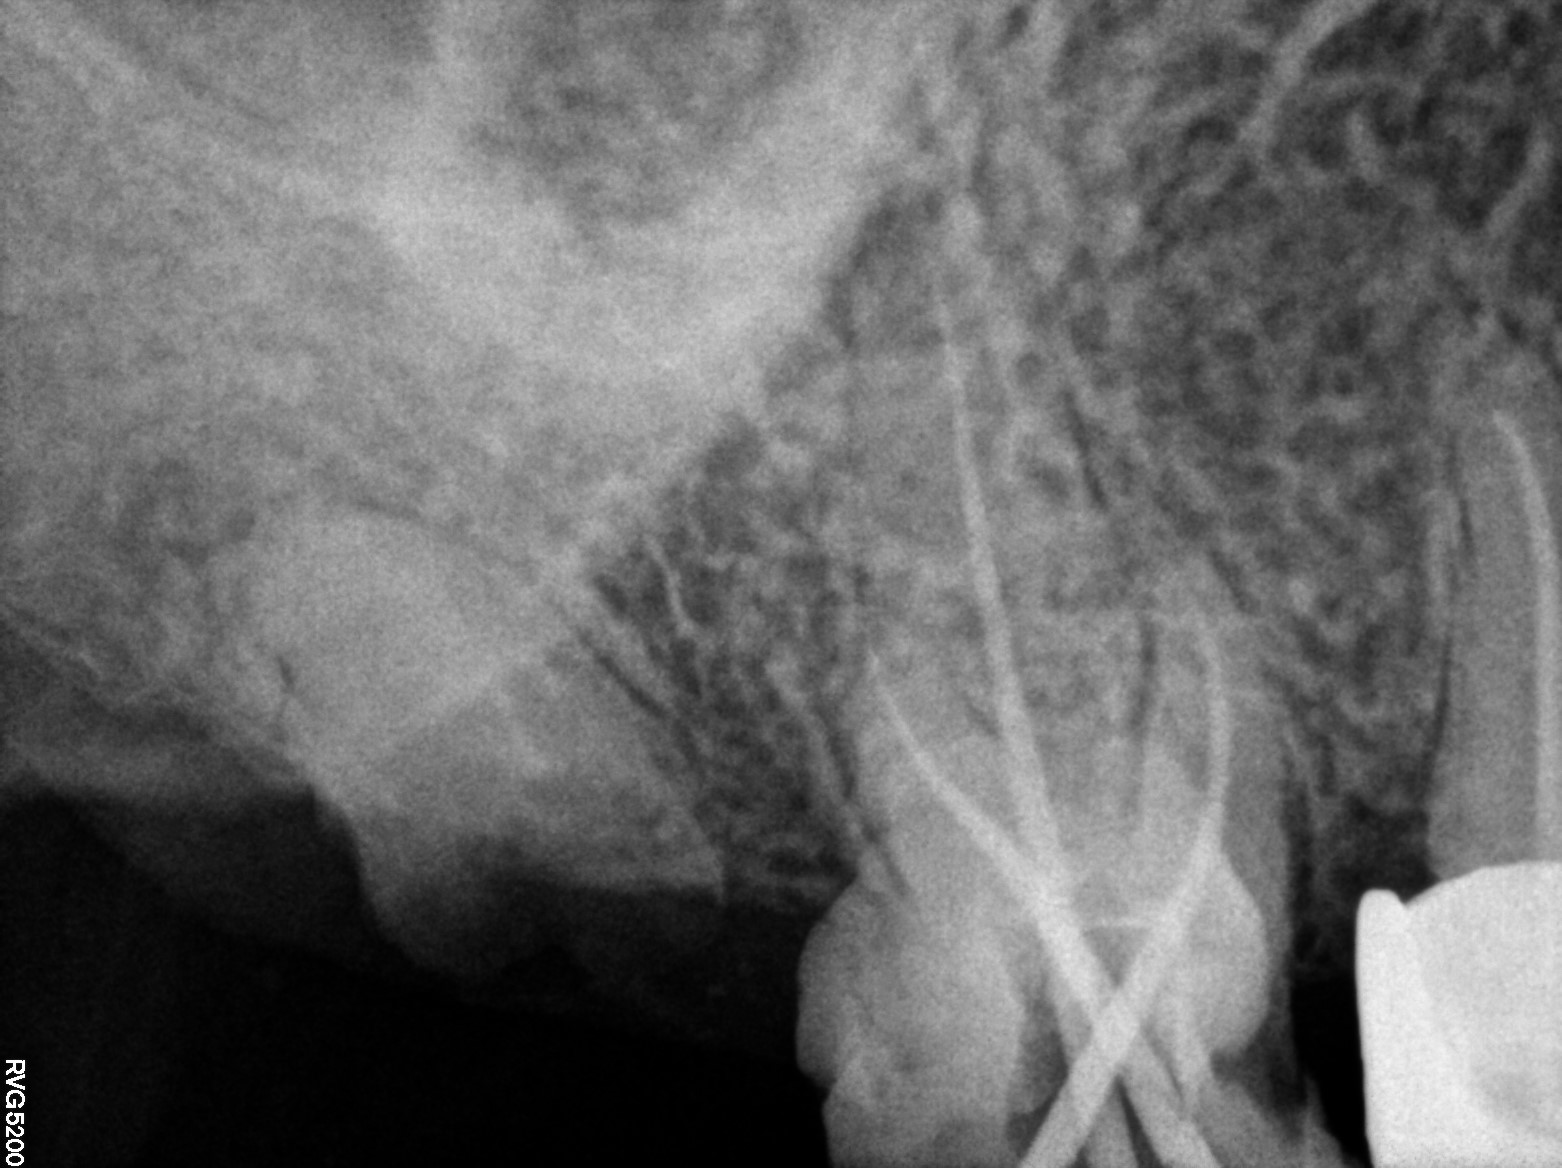

Dental Radiographs FHIR: DocumentReference · LOINC 24641-7

d (14).jpg

24641-7